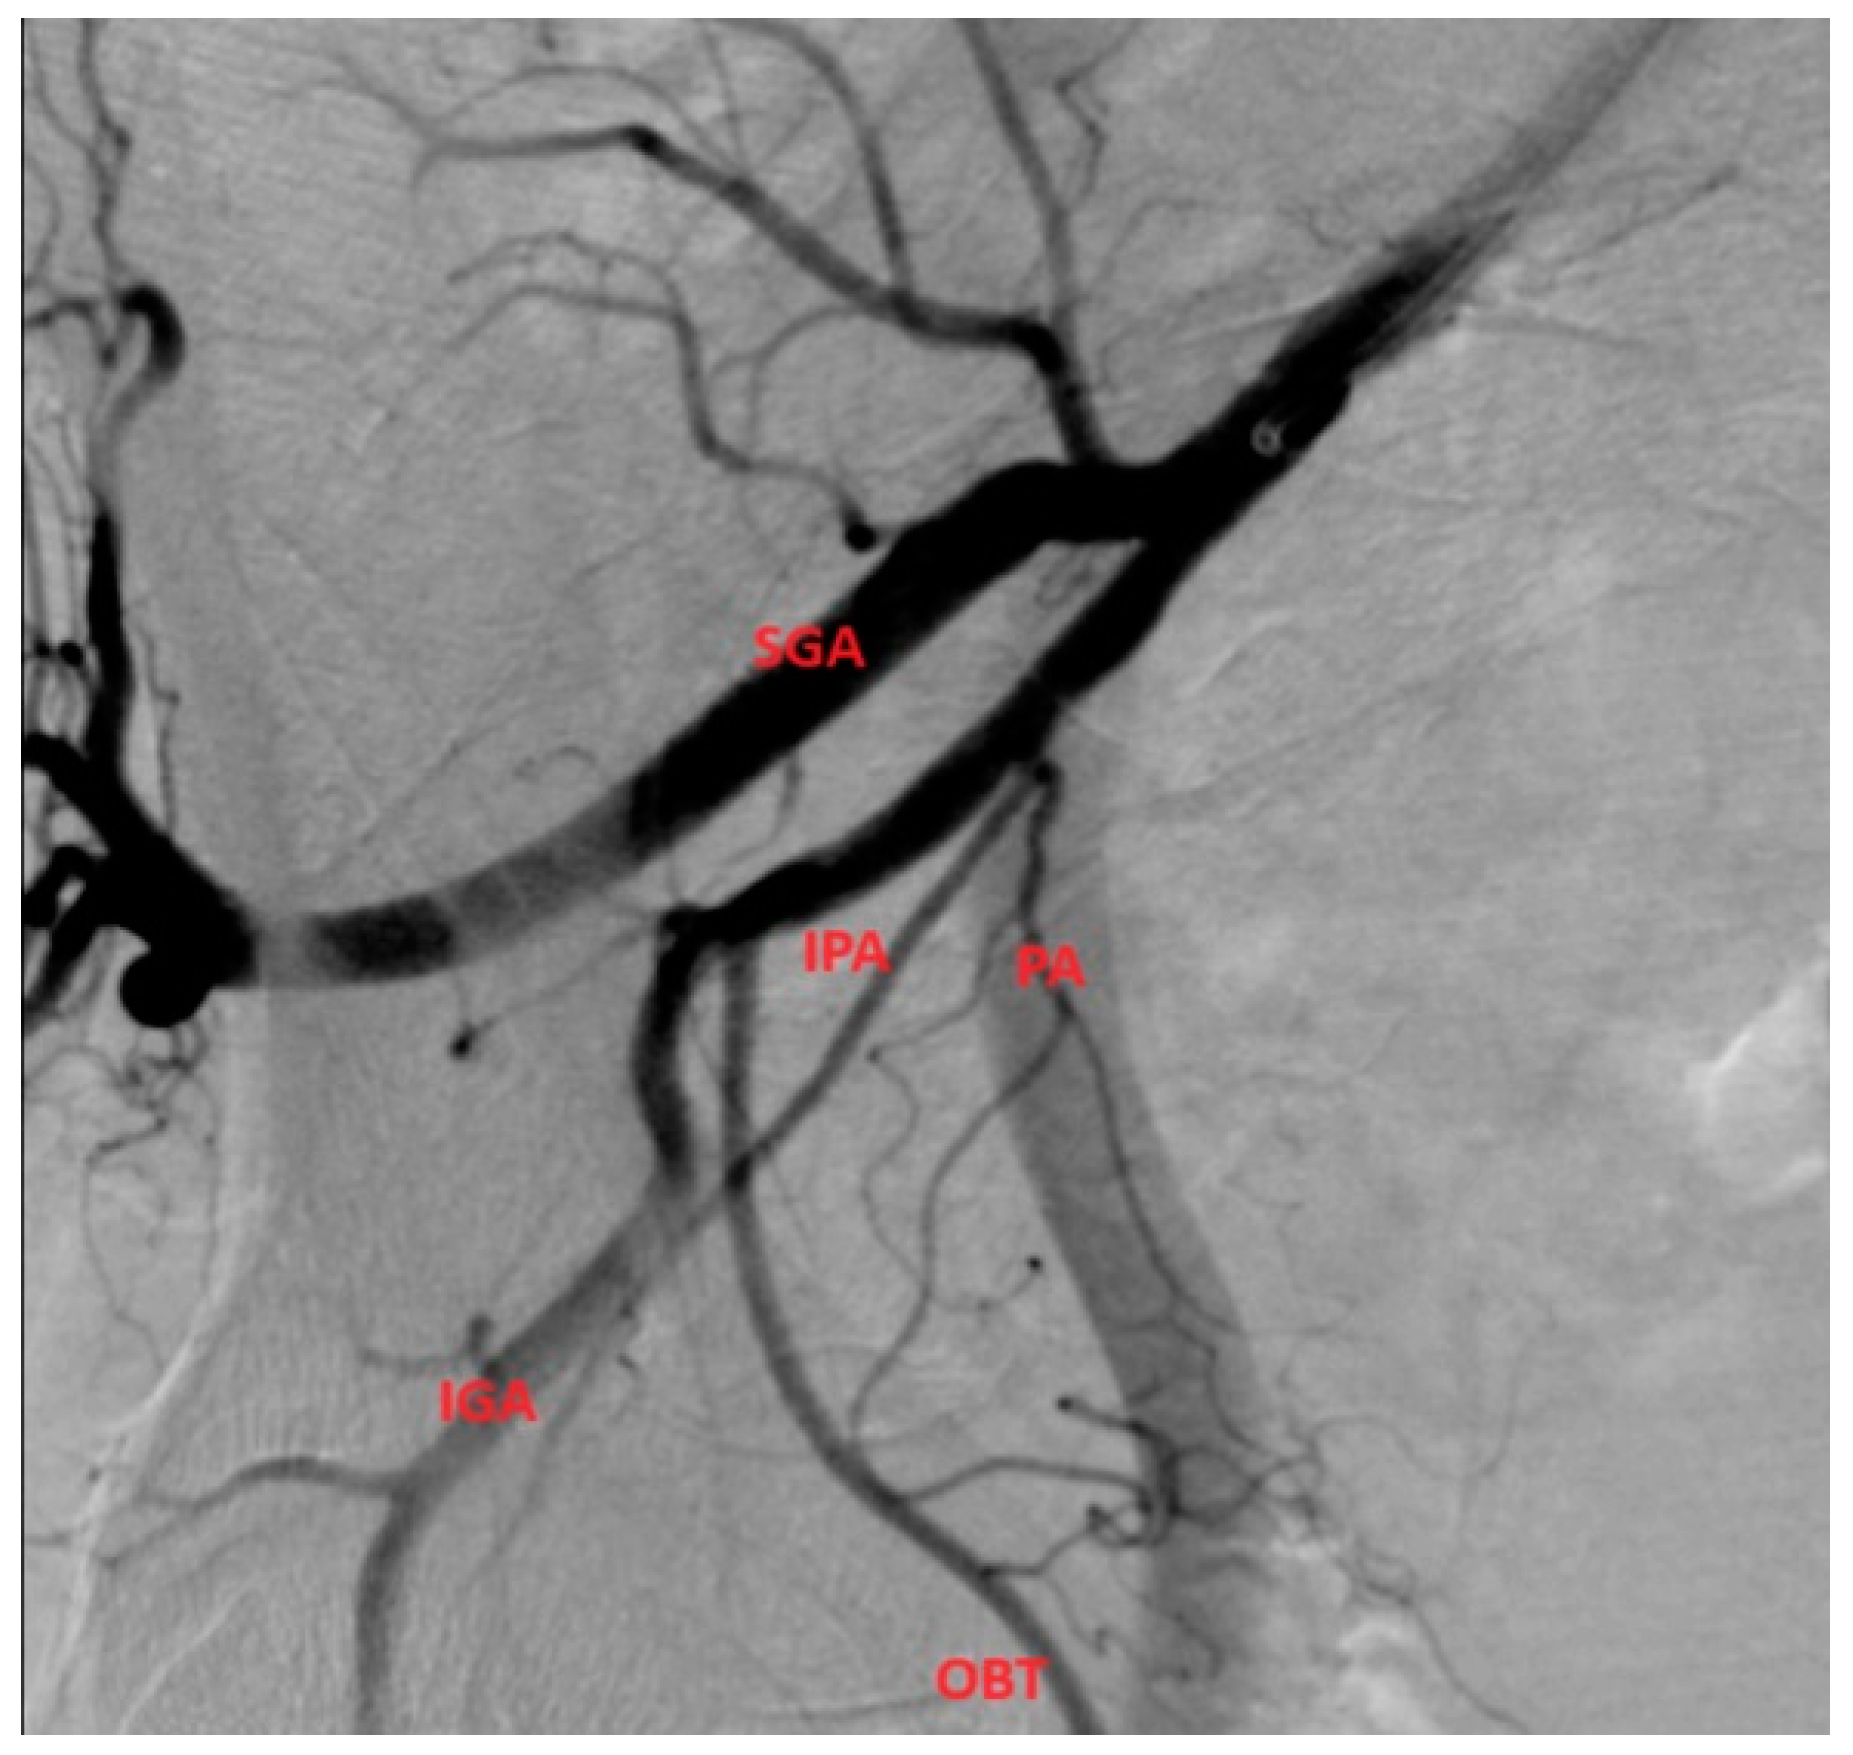

- After we identified the four main branches (superior gluteal artery, inferior gluteal artery, obturator artery, internal pudendal artery), we searched for the PA artery, which usually has a characteristic corkscrew aspect and parallel trajectory with the IPA.

- Type of internal iliac artery (IIA) branching pattern from Yamaki classification which helps to identify possible origins of the PA [3].